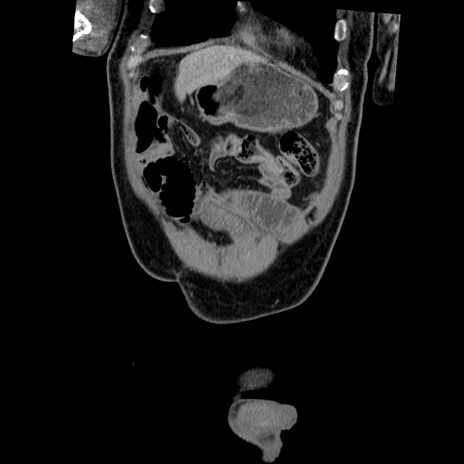

症例

横断像